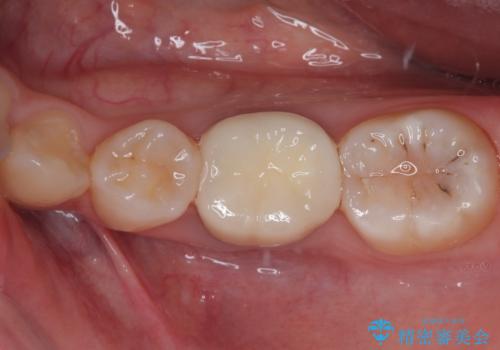

奥歯も著しく茶色に変色していたため、同様にオールセラミッククラウンにて補綴治療を行うこととしました。

明るく自然な口元になりました。